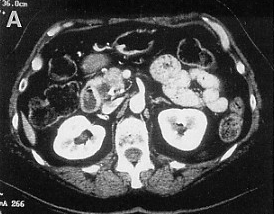

Mass in head of pancreas